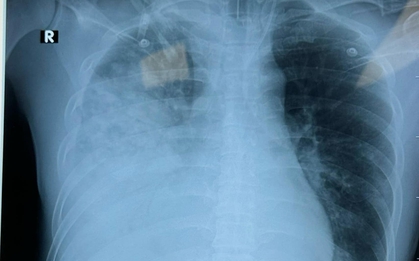

Người đàn ông sốt 40 độ C, phổi gần như "trắng xóa", chỉ vài ngày đã suy đa tạng: Thủ phạm liên quan đến thói quen nhiều gia đình vẫn mắc

Một chiếc điều hòa lâu ngày không được vệ sinh có thể tiềm ẩn rủi ro sức khỏe nghiêm trọng mà nhiều người không ngờ tới.

Bé trai 12 tuổi "phổi trắng xóa" chỉ sau 1 ngày mắc cúm: Cách phát hiện sớm cúm nặng ở trẻ

Một bé trai 12 tuổi nhiễm cúm A chủng H3N2, chỉ sau 24 giờ hình ảnh phổi đã xuất hiện tình trạng viêm lan tỏa nghiêm trọng, còn gọi là "phổi trắng".

Người đàn ông 40 tuổi có phổi trắng xóa, nguyên nhân đến từ một thứ rất quen mặt

Vốn là người có thể trạng khỏe mạnh nhưng anh Nam không ngờ có ngày mình phải nhập viện trong tình trạng nguy kịch bởi 1 căn bệnh mà anh coi là "bệnh xoàng".